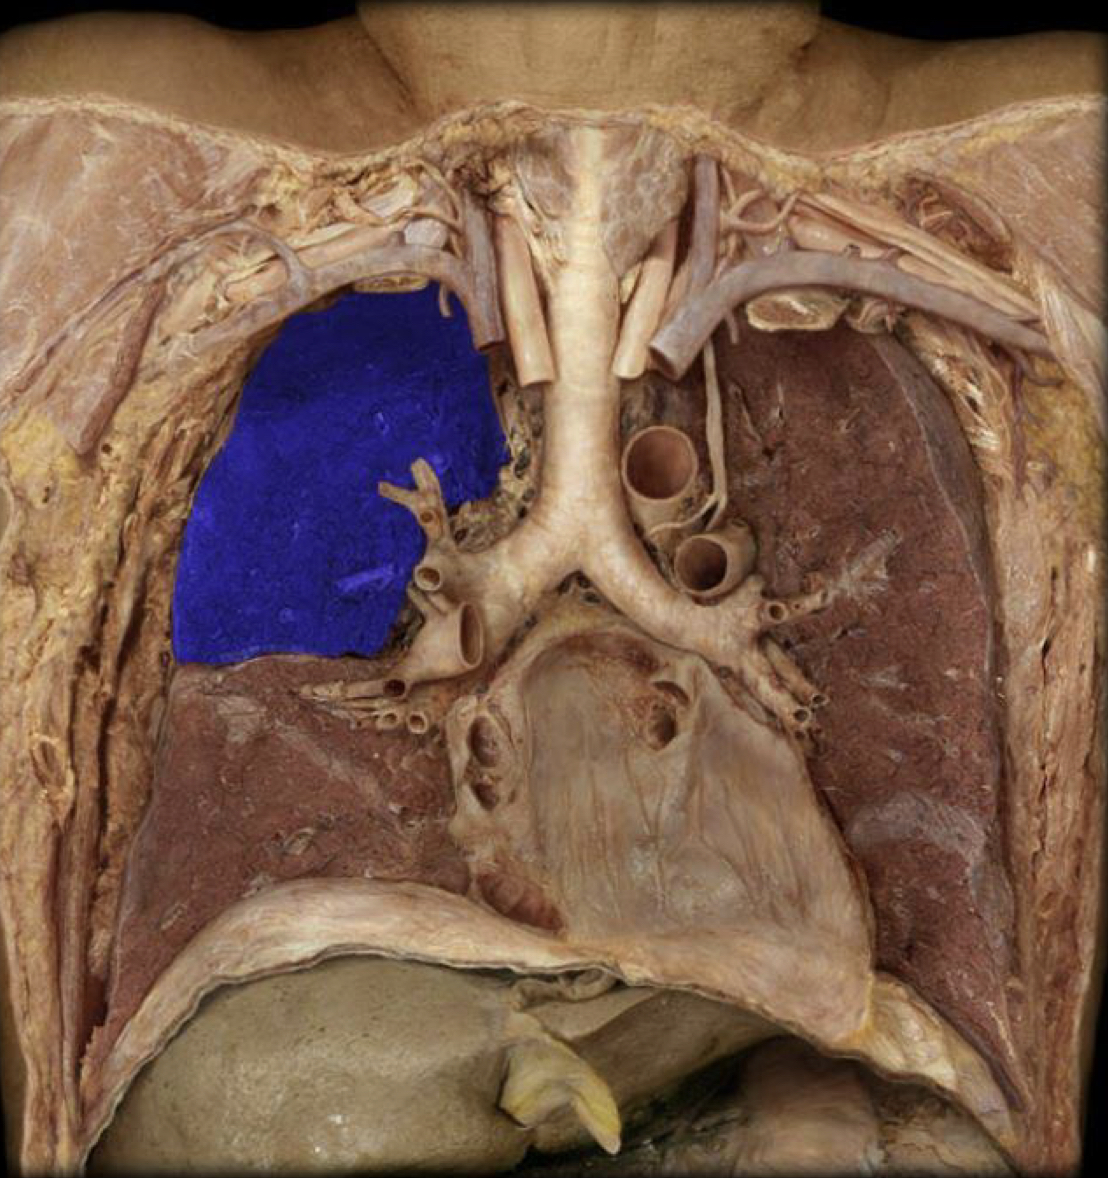

New cards

What structure is highlighted in blue?

Right lung

Left lung

Superior lobe of Right lung

Middle lobe of Right lung

Inferior lobe of Right lung